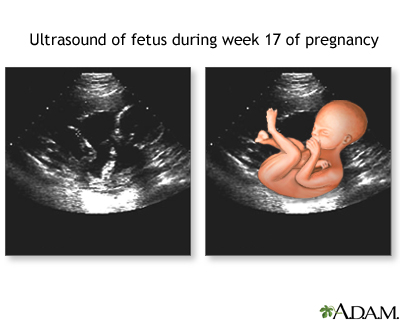

During seventeen to twenty weeks of development, fetal movements known as quickening are commonly felt by the mother.